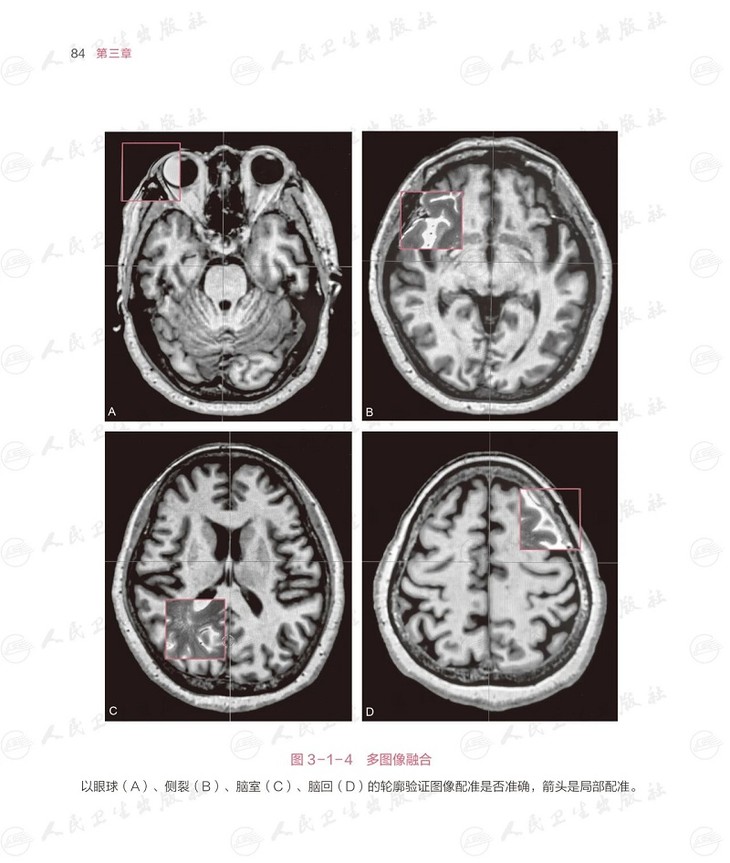

本书把帕金森病脑深部电刺激术相关的每个细节,从术前的评估,到包含两百余个步骤的手术过程,到程控的原理和方法,用形象的绘图,展示每个细节。本书的编撰凝聚了帕金森病脑深部电刺激术治疗领域 专家团队的心血,插图之精美,让人读来赏心悦目,学来受益匪浅。对于基层医生而言,本书无疑是提升专业技能、强化医患沟通意识的宝贵资源,值得细细研读。本书特联合国内比较有代表性的专家,以帕金森病为例,集各家所长,结合各大医院的方法,把精细的评估、精准的植入和个体化的程控做出 解读。